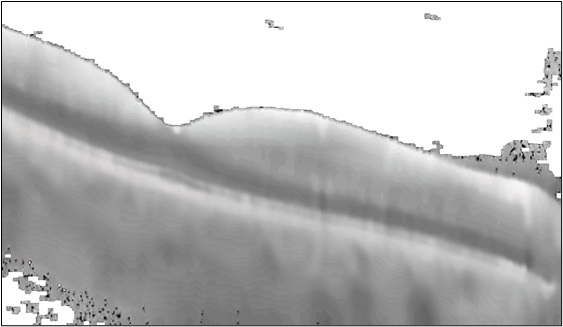

Figure 12 depicts the correctly classified AD patient input OCT image, segmented retinal OCT image in dark mode, and the corresponding CAM image for subject AD439. Figure 12(a) is a minimally processed OCT scan of the retina. The shades of gray represent various layers and structures in the retina, with darker regions indicating less reflective areas. Figure 12(b) appears to be a binary or thresholded version of the OCT scan. In this representation, areas are segmented into black-and-white regions, possibly highlighting specific structures within the retina, particularly retinal layers. Figure 12(c) is a CAM heatmap showing the areas the model considers essential for classification. Red and yellow indicate regions with high activation, meaning these areas strongly influenced the model’s decision. The blue color represents areas with low activation.

Figure 13 depicts the correctly classified AD patient input OCT image, segmented retinal OCT image in dark mode, and corresponding CAM image for subject AD508. The CAM shows that the model concentrates on the correct retinal layers related to Alzheimer’s pathology, such as the RNFL and GCL, which undergo thinning or other structural changes in Alzheimer’s patients. The targeted region focuses on relevant retinal structures, suggesting the model has learned to identify areas clinically linked to the disease, improving classification accuracy.